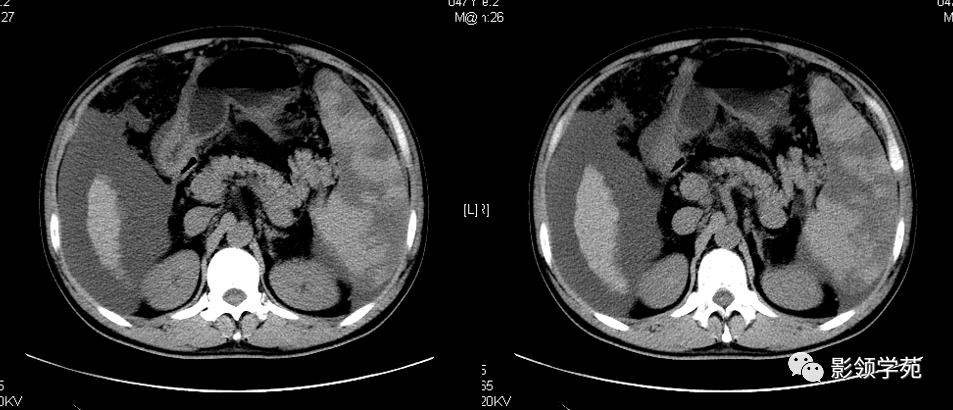

图片欣赏——清晰可见的副脾

副脾

副脾CT